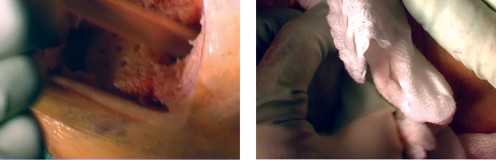

استبدال مفصل الركبة بالإسمنت: تفاصيل العملية

تُعد عملية استبدال مفصل الركبة بالإسمنت إجراءً دقيقًا يتطلب مهارة وخبرة عالية، وهو ما يوفره الأستاذ الدكتور محمد هطيف لمرضاه في صنعاء. تهدف العملية إلى إزالة الأسطح المفصلية التالفة واستبدالها بمكونات اصطناعية (غرسات) تُثبت في مكانها باستخدام إسمنت عظمي خاص.

التحضير للعملية

قبل الجراحة، سيقوم فريق الأستاذ الدكتور محمد هطيف بإجراء تقييمات شاملة، بما في ذلك الفحوصات المخبرية، تخطيط القلب، وتقييم التخدير. سيتم إعطاء المريض تعليمات حول الأدوية التي يجب إيقافها وتلك التي يجب الاستمرار فيها.